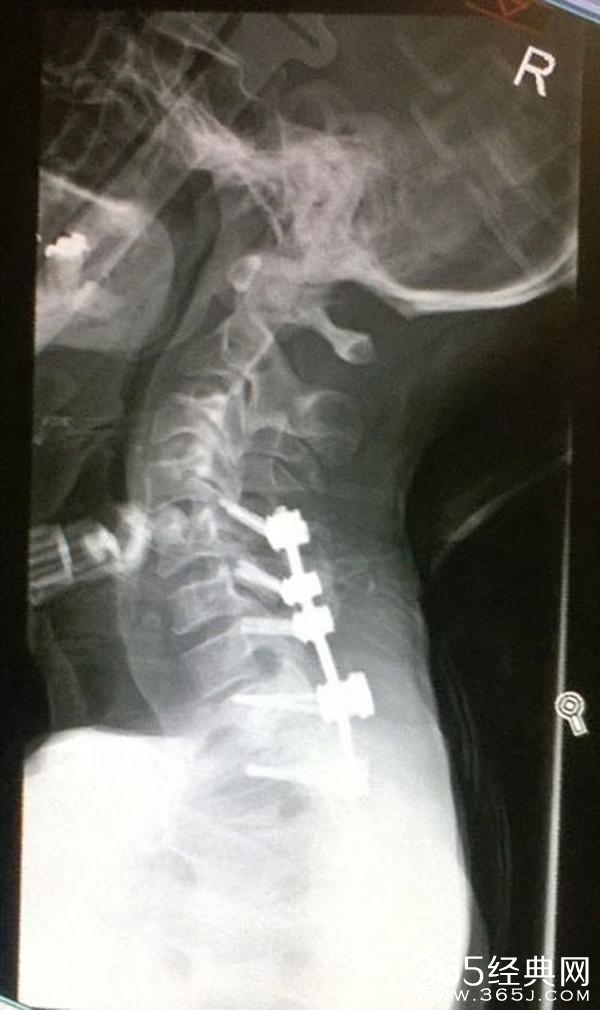

近日,英国的42岁露营爱好者史蒂文•希尔(Steven Hill)为了能欣赏到更壮美的风景,在120英尺(约合33米)高的悬崖边上搭帐篷野营,结果不慎踩空坠入悬崖。经过4小时的昏迷和醒来后40分钟的匍匐前行、挣扎求救,希尔最终在骑自行车路过的好心人的帮助下被送进了医院。

据希尔的诊治医生介绍,希尔这次伤势相当严重:他的肺部受到了损伤,身上有112根骨头被摔碎(包括脊柱);他这次能够劫后余生简直是一个奇迹。希尔的朋友们也会开玩笑说他是“机械战警”。